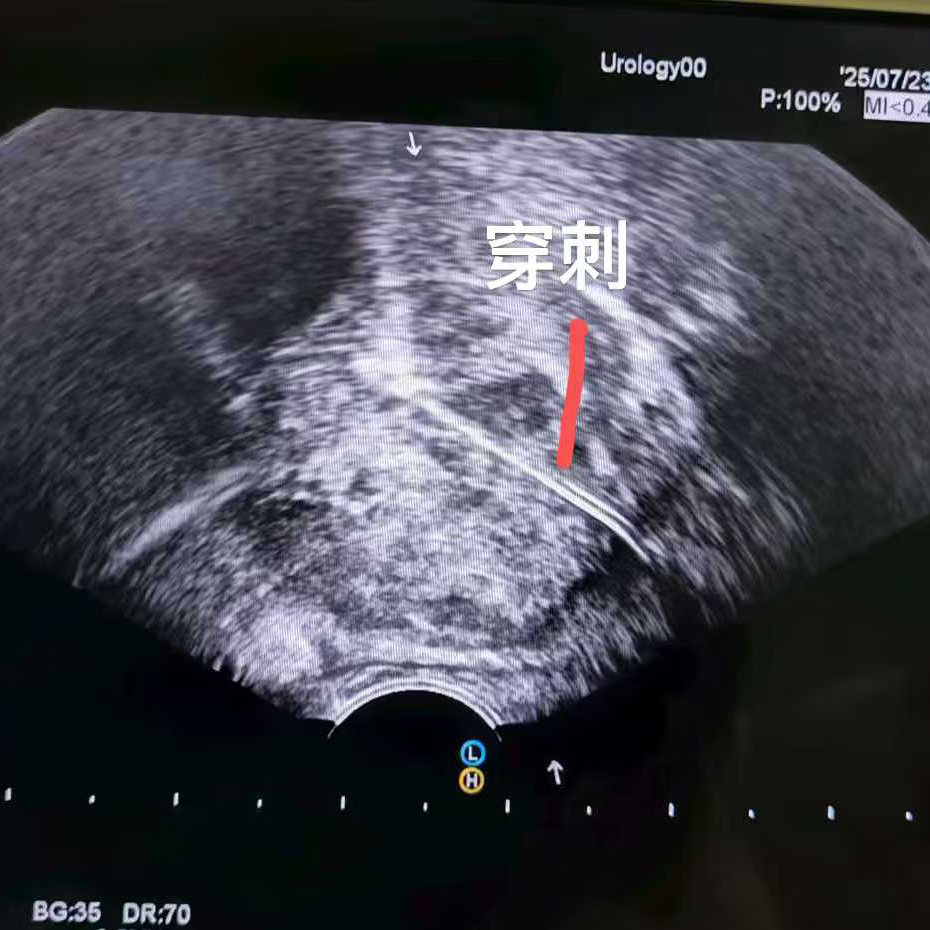

比如这位马来西亚患者,PSA指标正常,但影像却发现可疑病灶,结果穿刺证实是少见的前列腺尿路上皮癌,在我院接受了冷冻消融治疗。